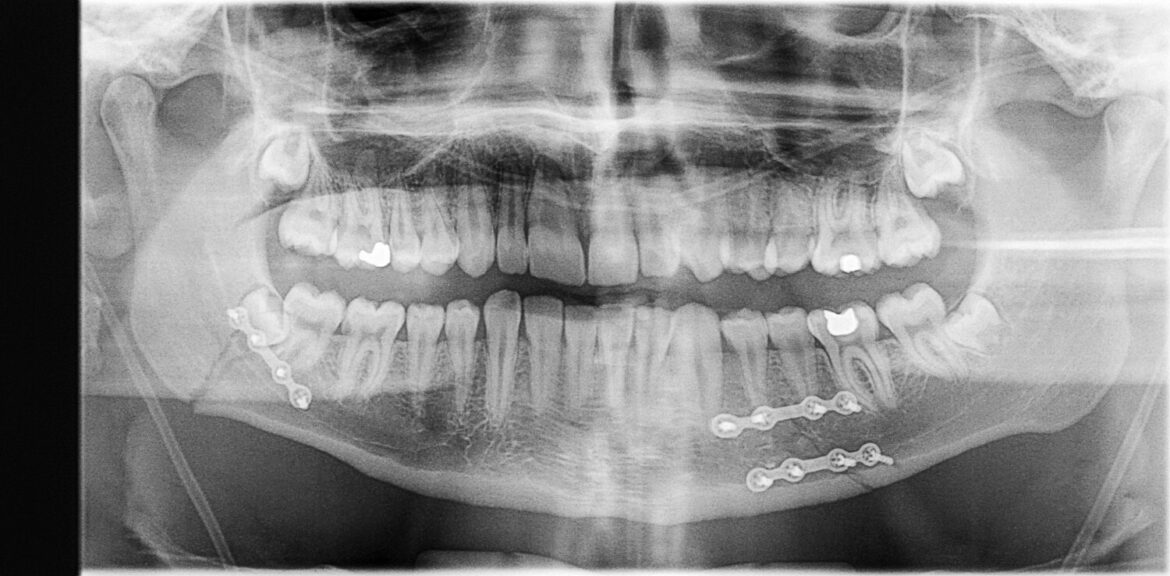

Dentists have noticed that the oral cavity has a very high regenerative potential. For example, in the place of a removed tooth, both the bone structure and the cartilage, epithelial structure and nerve tissues are rebuilt. Patients do not lose feeling within this part of the mandible or the palate.

“We hypothesized that the gum tissue is able to transform into other structures, especially a specific group of stem cells. We want to explore the possibilities of their use and find out what types of tissues can be made from them”, says project manager, Dr Eng. Agnieszka Gadomska-Gajadhur from the Faculty of Chemistry, Warsaw University of Technology.

The research will be carried out with a team from the University of Medical Sciences in Poznań, which will differentiate cells taken from porcine gums towards bone, cartilage or nervous tissue. The role of the PW team is to provide a carrier on which stem cells will be embedded and will be able to grow, transforming into tissue.